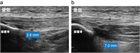

1. ジャンパー膝はジャンプやランニング動作を繰り返すスポーツ選手に好発する膝蓋腱近位部のスポーツ障害である。

1. ジャンパー膝の場合、超音波画像検査を行う事が推奨される(推奨度1)